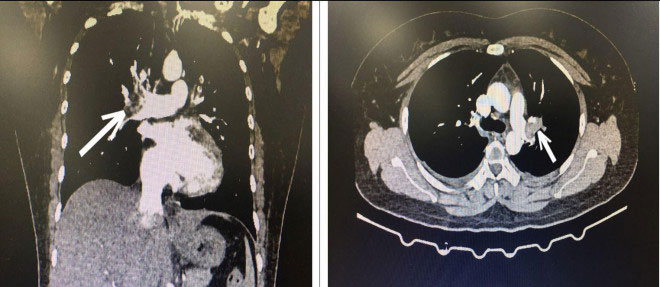

Hình ảnh CT lồng ngực bệnh nhân bị tắc động mạch phổi cấp tính. Ảnh BVCC

Bệnh nhân được chỉ định xét nghiệm cấp cứu, siêu âm tim có hình ảnh giãn buồng tim phải, hở nặng van 3 lá, tăng áp lực động mạch phổi, hướng chẩn đoán tới bệnh thuyên tắc động mạch phổi cấp và quyết định cho chụp CT ngực có tiêm thuốc cản quang, kết quả là hình ảnh huyết khối động mạch phổi 2 bên, chẩn đoán xác định là huyết khối thuyên tắc động mạch phổi cấp tính/lạm dụng thuốc tránh thai Levonorgestrel.